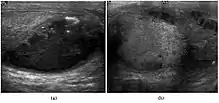

Teratoma Although teratoma is the second most common testicular tumor in children, it affects all age groups. Mature teratoma in children is often benign, but teratoma in adults, regardless of age, should be considered malignant. Teratomas are composed of all three germ cell layers, i.e. endoderm, mesoderm and ectoderm. At ultrasound, teratomas generally form well-circumscribed complex masses. Echogenic foci representing calcification, cartilage, immature bone and fibrosis are commonly seen [Fig. 5]. Cysts are also a common feature and depending on the contents of the cysts i.e. serous, mucoid or keratinous fluid, it may present as anechoic or complex structure [Fig. 6].

Fig. 5. Teratoma. A plaque-like calcification with acoustic shadow is seen in the testis.

Fig. 6. Mature cystic teratoma. (a) Composite Image. Mature cystic teratoma in a 29-year-old man. Longitudinal sonography image of the right testis shows a multilocular cystic mass. (b) Mature cystic teratoma in a 6-year-old boy. Longitudinal sonography of the right testis shows a cystic mass containing calcification with no obvious acoustic shadow.